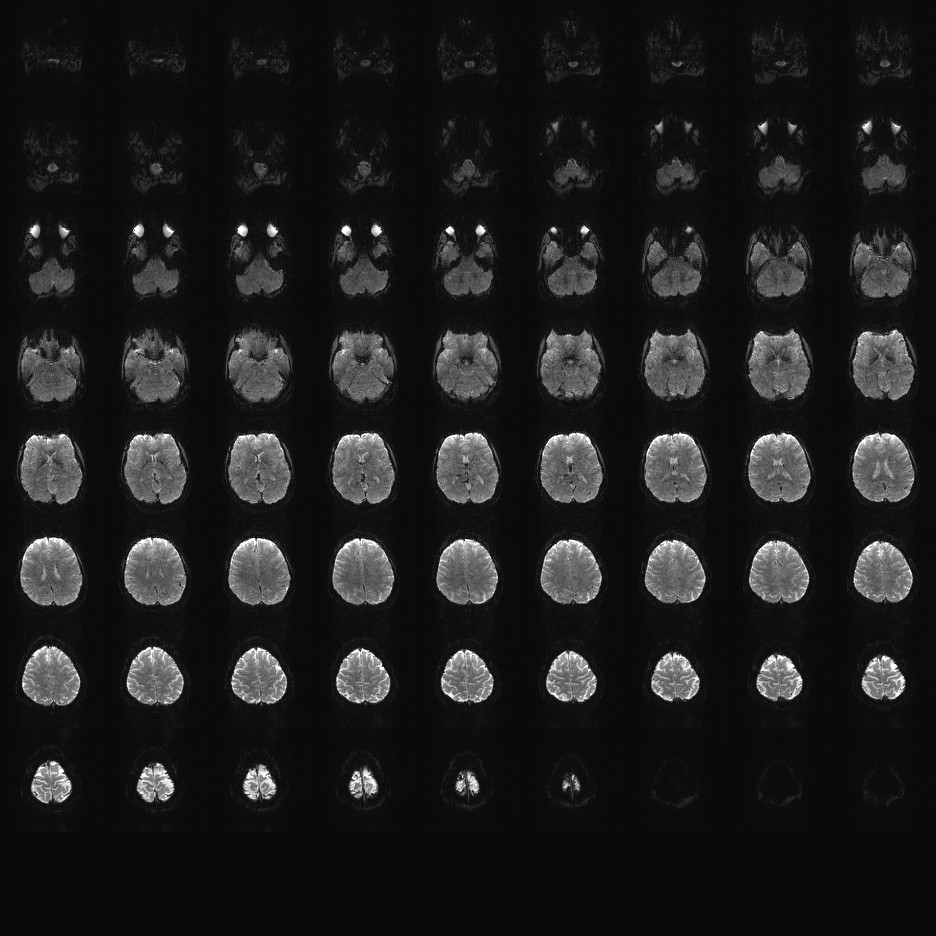

Multi-banded RF pulses can be used to accelerate volume coverage along the slice direction by simultaneously exciting and acquiring multiple slices and subsequently unaliasing them using parallel imaging principles and the spatial information available in multi-channel RF array coils.

This allows for a direct reduction in the volume TR by the number of simultaneously excited slices (i.e., the multiband (MB) factor or the slice acceleration factor).